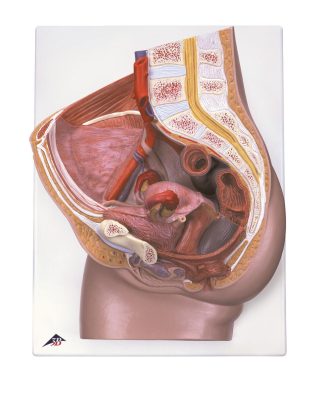

Innehåller 10 bilder som vid vinkling ändras och visar vad som händer i våra största organ i kroppen.

Innehåller bl.a. Hjärtat, Lungorna och hjärnan mm.